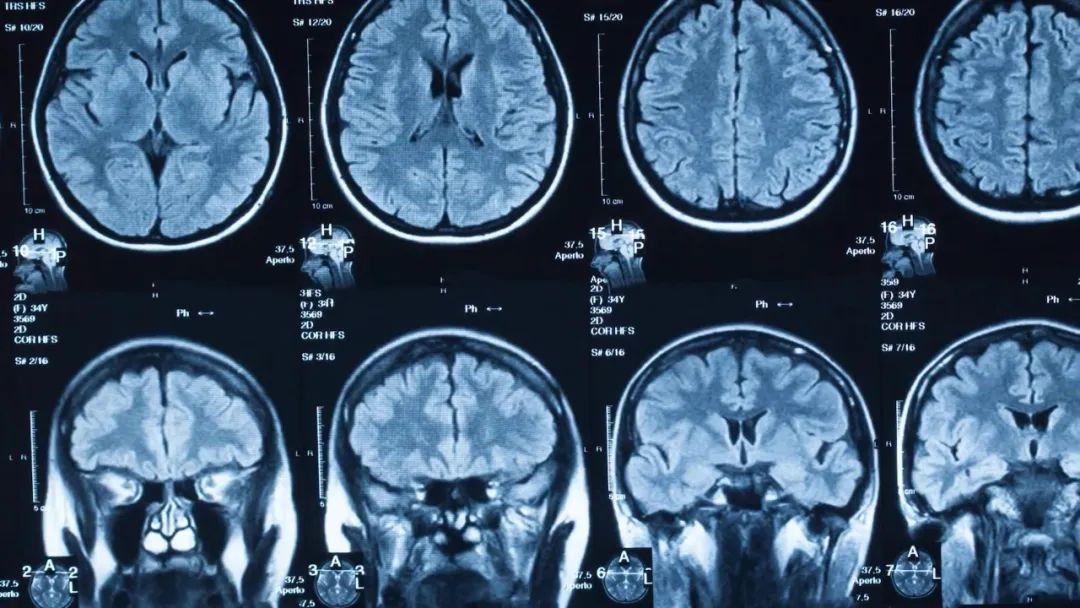

核磁共振成像是医学中应用最广泛的成像方法之一,由于担心人们认为其名称中的“核”与核辐射有关,因此将它重命名为磁共振。事实上,这个“核”与核辐射无关,只是用来描述产生共振的原子核,更准确来说应该是原子核的旋转。

对于人体中的核磁共振成像,通常以氢核为目标,因为其中水和脂肪中有很多,然后图像的亮度基本上可以告诉我们脂肪和水的数量。人们也可以瞄准其它原子核并进行测量,这就导致了不同核磁共振图像的工作方式不同。核磁共振成像非常适合于检查软组织,而对于骨折一般则使用X射线成像。

上述提到,共振频率与磁场强度成正比,正因为如此,我们可以使用磁场梯度来瞄准特定位置的原子核,生成不同位置的身体切片图像。